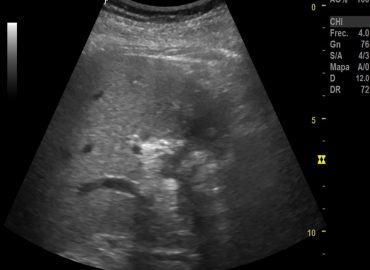

Paciente: masculino Edad: 11 años. Motivo de consulta: dolor abdominal. App: traumatismo.